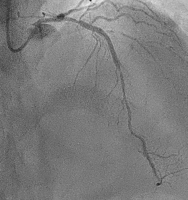

Angiography

Abbildung 2: Follow-up angiography showed hazy lesion distal of the stent with significant luminal narrowing, followed by long diffuse lesion